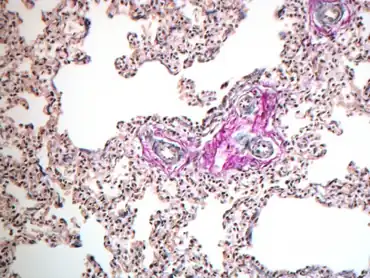

Persistent pulmonary hypertension of the newborn. The lung is immature (thickened interstitium with double capillary loops)

To help with diagnosis, the clinician can watch out for predisposing factors, such as: birth asphyxia, meconium aspiration, use of NSAIDs (non steroidal anti-inflammatory drugs) and SSRIs (selective serotonin reuptake inhibitors) by the mother, and early onset sepsis or pneumonia.[8] To diagnose a fetus with pulmonary hypertension, PVR must be higher than systemic vascular resistance, resulting in high afterload and decreased systemic blood flow. This causes a significant decrease in oxygen concentration, which clinically manifests as insufficient blood flow to the lower body, while there is adequate circulation to the head and right side of the body.[9] Other echocardiographic findings in PPHN include right ventricular hypertrophy, deviation of the ventricular septum, tricuspid regurgitation, and shunting at the patent foramen ovale.[3]